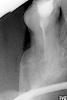

sergnew Опубликовано 8 сентября, 2012 Поделиться Опубликовано 8 сентября, 2012 http://s013.radikal....c5d06ae9f83.jpgПлохо депульпировали зубы что делать? Оцените, пожалуйста, снимок. Ссылка на комментарий

Magdalena Опубликовано 9 сентября, 2012 Поделиться Опубликовано 9 сентября, 2012 Однозначно перелечивать, если честно, сомневаюсь в целесообразности сохранения 6 верхнего зуба, уж очень мало там кости осталось. Ссылка на комментарий